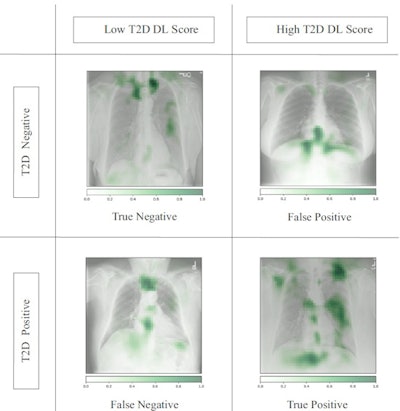

Occlusion maps identifying key features in representative chest x-rays with high and low diagnostic scores. Dark green pixels highlight significant features for model prediction, primarily associated with cardiomediastinal, upper abdominal, lower neck, and supraclavicular regions. Examples of CXRs with high and low diagnostic scores are presented. Image and caption courtesy of Nature Communications through CC BY 4.0.

Occlusion maps identifying key features in representative chest x-rays with high and low diagnostic scores. Dark green pixels highlight significant features for model prediction, primarily associated with cardiomediastinal, upper abdominal, lower neck, and supraclavicular regions. Examples of CXRs with high and low diagnostic scores are presented. Image and caption courtesy of Nature Communications through CC BY 4.0.The prospective test dataset of 9,943 images included 8,382 (84.3%) patients with no type II diabetes, 1,119 (11.3%) who had controlled disease, and 442 (4.4%) with poorly controlled disease. According to the findings, the model effectively detected type II diabetes with an area under the receiver operating curve (AUC) of 0.84 and a 16% prevalence. The model flagged 1,381 cases (14%) as suspicious for type II diabetes.

Finally, the authors noted that the occlusion maps generated to display the basis for the DL model's decisions corresponded significantly to known fat distribution features for the disease in the central chest, lower neck, upper abdomen, and axillary regions.